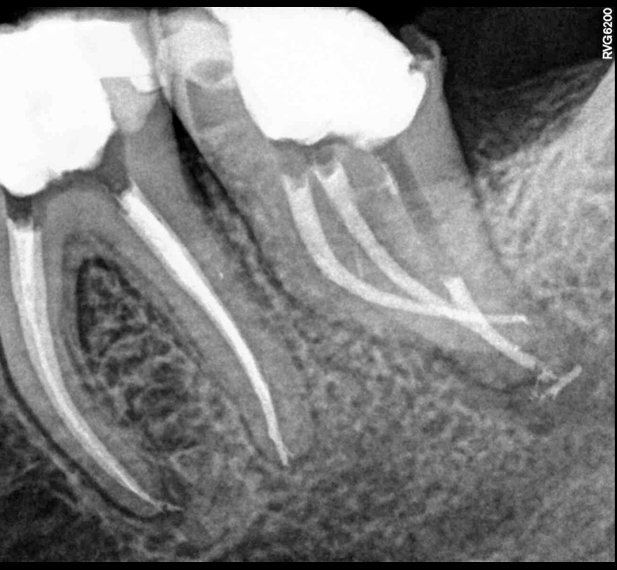

I casen, der er præsenteret i videoen herunder, bliver en endodontisk behandling udført af tand nr. 37 under anvendelse af den ekspanderbare XP-teknologi.

XP Shaper-filen bliver justeret til korrekt arbejdslængde og indsat i kanalen for at nå rodmålet i 3-5 lange op-/nedbevægelser. Herved udvides kanalen til en størrelse 30/.01. Som næste trin introduceres XP Shaper-filen i kanalen igen, og der udføres 15 lange op-/nedbevægelser. Dette gør det muligt for filen at udvide sig til en størrelse på minimum 30/.04. Herefter testes om en guttaperkapoint 30/.04 passer til rodmål. En 3D-rengøring af de uberørte områder i kanalerne udføres ved hjælp af XP Finisher-filen i lange op-/nedbevægelser i 1 minut pr. kanal. Som et sidste trin – efter tørlægning af kanalerne - udføres rodfyldning med en enkelt guttaperkapoint og den biokeramiske sealer TotalFill (FKG Dentaire, Schweiz). Slutteligt bliver der udboret til stift i den distale kanal og der gøres klar til rodstift og opbygning.